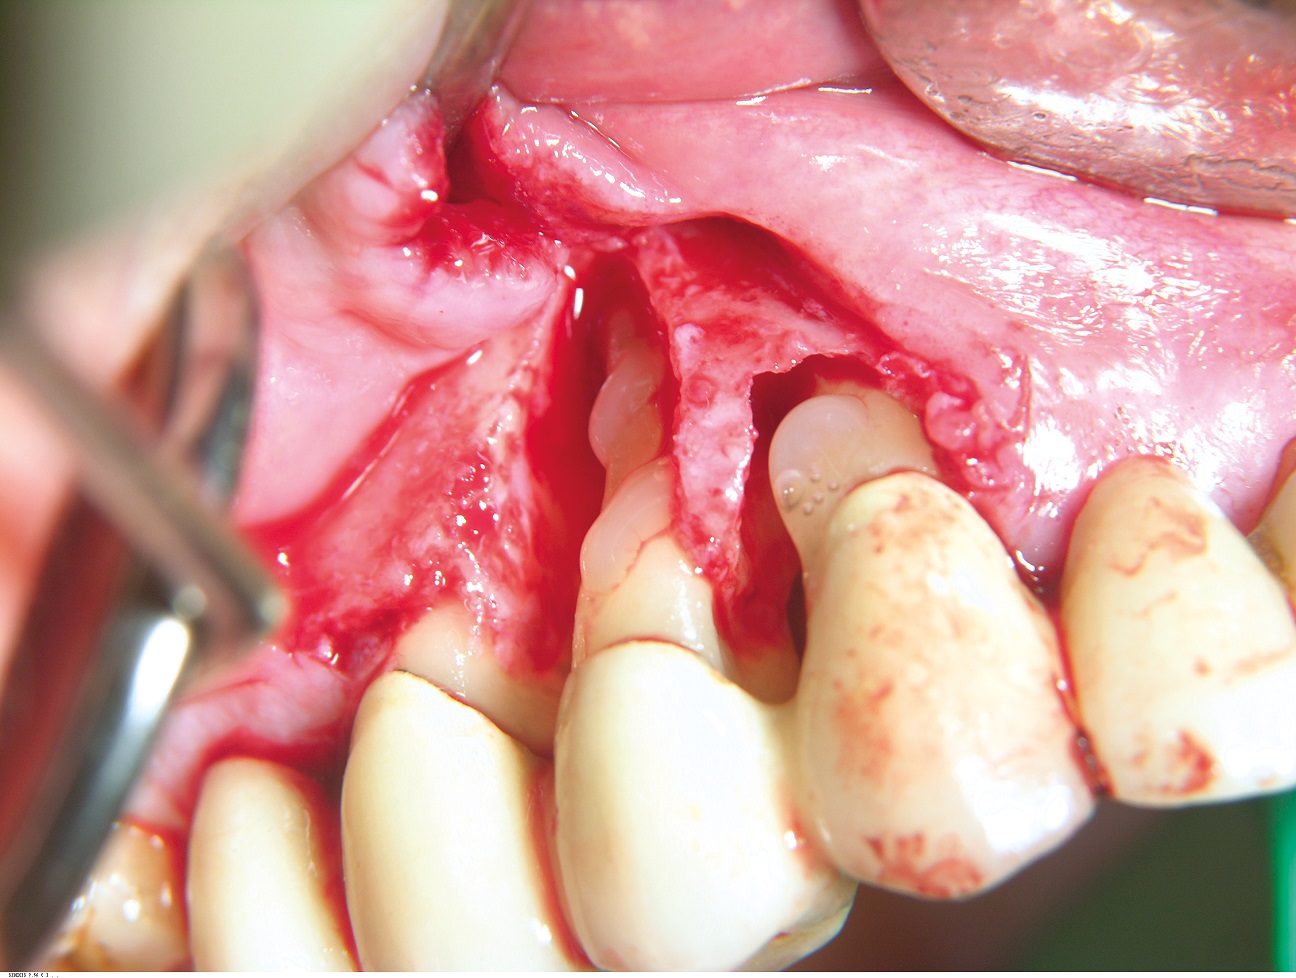

02/10 - Pre-operative clinical situation.GTR for the treatment of a deep three-dimensional intrabony defect using cerabone®, collprotect® membrane and Straumann® Emdogain® - Dr. T. Schwaar